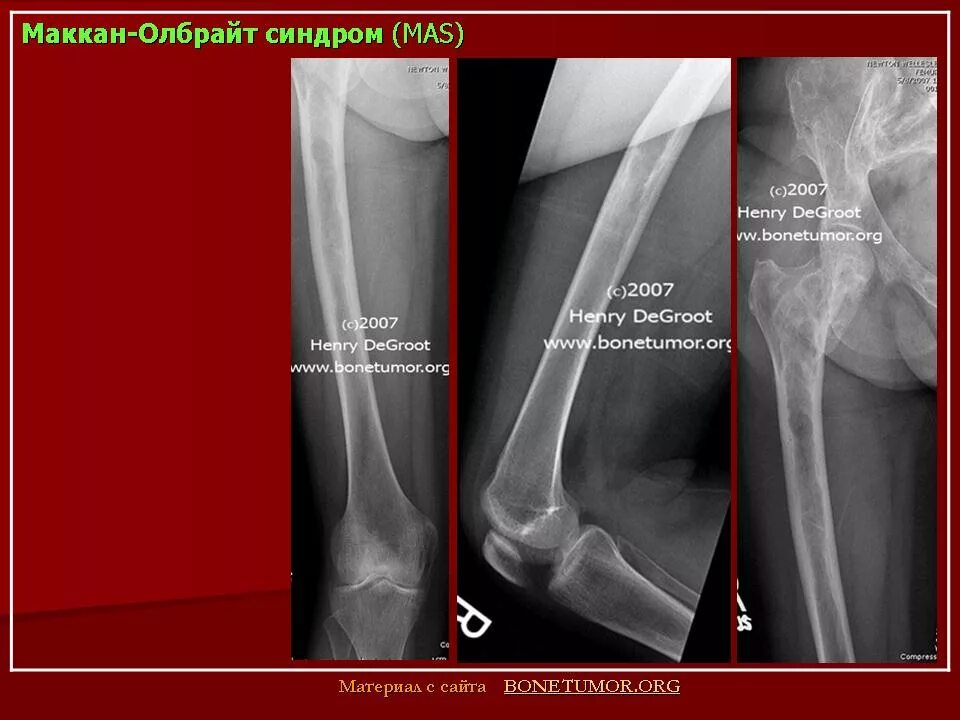

Синдром олбрайта